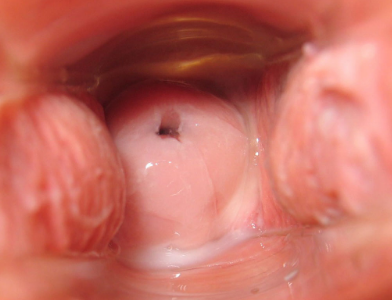

La patología del cuello uterino